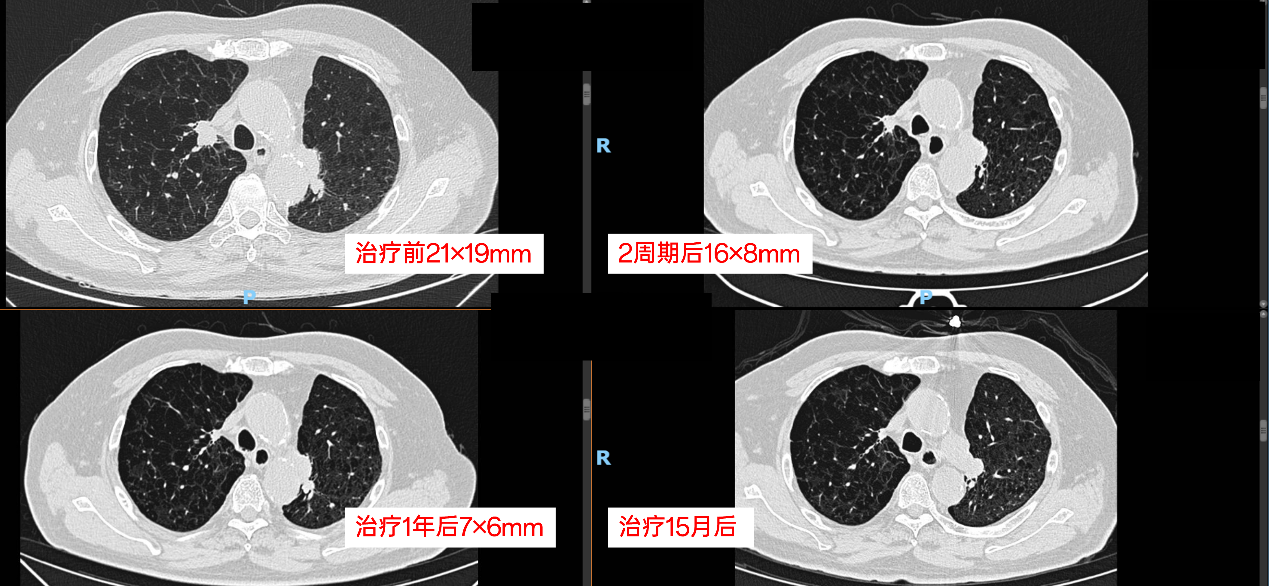

2022-10至2024-12-12期间,行舒格利单抗联合白蛋白紫杉醇6期治疗,后舒格利单抗维持治疗35周期。

疗效评估:

2022-12复查CT:1. 左肺上叶术后改变,右肺上叶尖段纵隔旁实性结节,现大小约16mm×8mm,较前缩小2. 慢支、肺气肿。

2023-03复查CT:1. 左肺上叶术后改变;右肺上叶尖段纵隔旁实性结节,现大小约7mm×6mm,较前缩小;原左肺上叶舌段结节,现片未见,另双肺数枚小结节,大致同前,随访。2. 左肺门及纵隔数枚淋巴结,同前相仿。3. 慢支、肺气肿;主动脉及冠脉硬化,心包少许积液,大致同前。4. 肝S6小囊肿;双肾数枚囊肿;两侧肾上腺结节样增粗;大致同前。5. 前列腺钙化;阑尾粪石;横结肠、降结肠多发憩室。